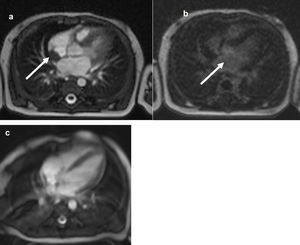

Blood tests showed: aregenerative normocytic anaemia (7.7 g/dL of hemoglobin), elevated C-reactive protein (160 mg/L), elevated white blood cells (28 G/L) with a high lymphocytosis (13 G/L). Liver tests showed mild cytolysis without cholestasis. Chest X-Ray was normal. Urine cytology and culture, lumbar fluid tests and culture, repeated blood cultures, and viral serologies were negative. Empirical antibiotic treatment with amoxicillin/clavulanate was initiated, then replaced by cefotaxime for six days without improvement. Because of the persistence of fever despite antibiotic treatment, other infectious causes were investigated: a 99mTc-diphosphonates scintigraphy showed a left wrist hyperfixation, and the further wrist X-Ray diagnosed a periostitis and osteomyelitis of the radius (Fig. 1), but the lesions were too small for biopsy. The antibiotics were then replaced by cefazolin and clindamycin for six days. MRI of the left wrist did not confirm osteomyelitis; so, antibiotics were discontinued. Echocardiography showed an intracardiac mass (15 × 8 mm) on the posterior wall of the right atrium extending to the origin of the superior vena cava. Cardiac MRI showed an intracardiac mass attached to the posterior wall and interatrial septum with a T2 hypo-signal, without enhancement after gadolinium injection (Fig. 2). Three hypotheses were considered: a right atrial myxoma (unlikely, however, due to non-enhancement after gadolinium injection), thrombosis of the superior vena cava, or a large Chiari network, which is a fenestrated, net-like embryonic remnant of the sinus venosus valves. One month later, in view of the finding of multifocal involvement, and persistent fever with persistent lymphocytosis elevation of liver enzymes, toxoplasmosis and syphilitic serology were performed. The Treponemal Hemagglutination Assay (TPHA) was superior to 10,240 and the VDRL (non-treponemal agglutination assay) was equal to 1:32. A new test on the mother revealed positive VDRL (1:8) and TPHA (> 10,240) tests. This child was born into a family with a low economic and social status, and the mother later reported several sexual partners. The infant was treated for 10-days with penicillin-G, administered at a dose of 250,000 units/kg/day, as recommended.4 Fever subsided on the first day, but a study of lymphocyte count and CRP showed that the inflammation had not been resolved. Thirteen days after the end of antibiotics, a second antibiotic course was prescribed: penicillin-G, administered at a dose of 150,000 units/kg/day for 15-days. Then a third cure was prescribed 10-days after the end of the second one, with the same posology. The effect of this prolonged antibiotic therapy led to a negative CRP and good infant health. However, the right atrial mass did not decrease and hyperlymphocytosis persisted. The infant was discharged after 4-months in hospital.

Cardiac-MRI comparison of intracardial mass (arrow) between the diagnosis and (a‒b) 20-months follow-up (c). T2 TrueFISP Sequence: Right intra-auricular mass at T2, attached to the posterior surface of the atrium and to the posterior part of the inter-atrial septum. Sequence after gadolinium injection: No lesion enhancement. Complete regression of intra-atrial mass.